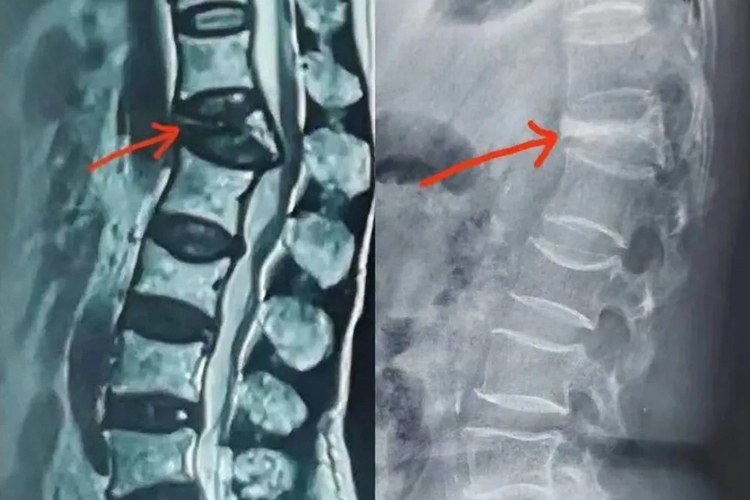

L2椎体骨折通常经X线检查确诊,可出现正平位置变扁,还可出现楔形变、骨质断裂,前缘可见小骨片分离,部分患者还可出现L1棘突骨折。